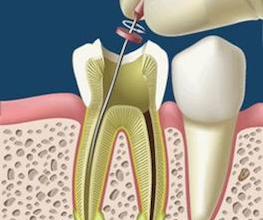

Endodoncia

Endodoncia